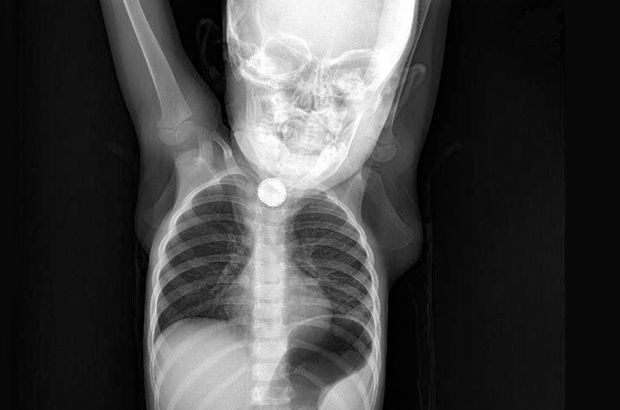

Batman’da Sevim ve İbrahim Ramazanoğlu çiftinin kusma ve ishal şikayetiyle hastaneye götürdüğü kızları Berfin’in (1,5) yassı pili yuttuğu belirlendi. Yemek borusunda ciddi yanıklar meydana gelen Berfin’in boğazının alt kısmındaki pil, operasyonla alındı.

DHA’nın haberine göre; Batman’da yaşayan Ramazanoğlu çifti, bulantı, iştahsızlık ve ishal beliren kızları Berfin’i Batman Devlet Hastanesi’ne götürdü. Doktorun muayene ettiği Berfin’in yemek borusunda cisim tespit edildi. Bunun üzerine Berfin, Elazığ Fırat Üniversitesi Hastanesi’ne sevk edildi. Burada yapılan kontrolde yassı pil yuttuğu tespit edilen Berfin, ameliyata alındı. Küçük kızın boğazının alt kısmındaki pil, başarılı operasyonla çıkarıldı. Ramazanoğlu çifti ise kızlarının, yaklaşık 3 ay önce yerde oynarken, bir cisim yuttuğunu hatırlayınca, pil yutmuş olabileceğini söyledi.

Operasyonu gerçekleştiren Tıp Fakültesi Çocuk Gastroenteroloji, Hepatoloji ve Beslenme Bilim Dalı Başkanı Prof. Dr. Yaşar Doğan, “Tanı amaçlı yaptığımız endoskopi neticesinde, Berfin´in, yassı bir pil yuttuğunu belirledik. Pili çıkardıktan sonra uzun süre orada kalmasından dolayı yemek borusunda ciddi yanıklar meydana gelmişti. Hatta bu yanıklar nerdeyse nefes borusuyla birleşecek şekilde bir oluşuma gidecekti. Hastamız şu an sağlığına kavuştu. Kliniğimizde şu an oral beslenmeye geçildi. Yarın taburcu etmeyi düşünüyoruz. Yine takiplerimiz devam edecek” dedi.